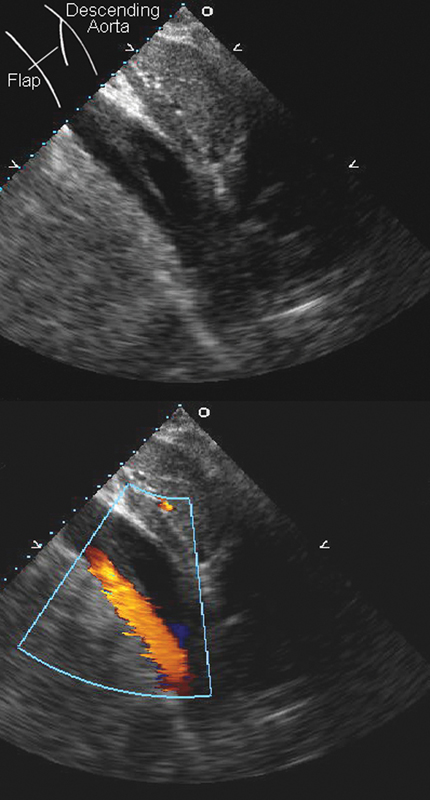

فحوصات تشخيصية لبعض امراض القلب والشرايين التاجية